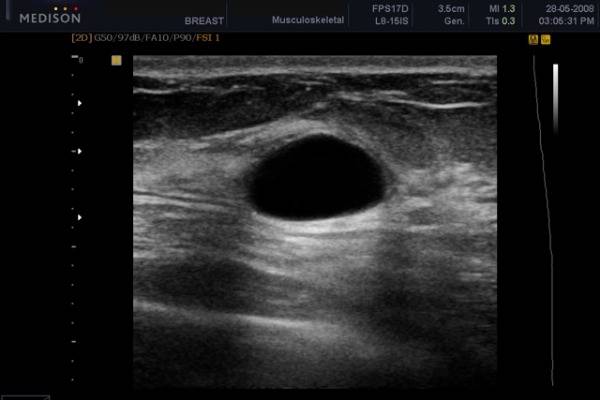

Киста. На УЗИ видны хорошо различимые образования с гладкими и четкими стенками. Внутри имеется жидкое содержимое (темный цвет). Киста сжимается под действием аппарата.

Для проведения дифференциальной диагностики с маститом таким женщинам рекомендовано прохождение УЗИ грудных желез. Обычно врачи-сонологи описывают расширение протоков, наличие в них большого количества секрета, усиление кровотока.

Основная цель ультразвукового исследования в маммологии – диагностика жидкостных и акустических плотных образований в груди, а также видимый контроль за лечебными и инвазивными манипуляциями. УЗИ диагностика является эффективным способом определить лактостаз. Сканограммы отражают застой в виде чрезмерно расширенных протоков молочной железы. Особенно четко можно увидеть расширение отдаленных протоков и синусов. При лактостазе, в отличие от мастита, наблюдается сохранение структуры молочной железы при отсутствии примесей крови и лимфы в тканях.